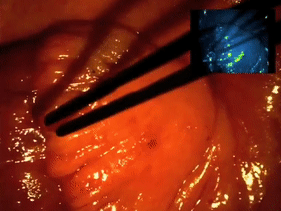

圖1:世界首例熒光導(dǎo)航卵巢癌切除術(shù)(ref.1)

在一項卵巢癌臨床試驗中【ref.1】,研究者將該探針用于術(shù)中實時探測腫瘤,結(jié)果表明,EC17 的特異性高達(dá) 100%,也就是說所有過表達(dá) FR-α 的惡性腫瘤均有熒光;而不表達(dá) FR-α 的腫瘤或良性腫瘤則沒有熒光。另外熒光圖像能幫助醫(yī)生發(fā)現(xiàn)更多腫瘤病灶,數(shù)量約為可見光的 5 倍。

圖 4:EC17 引導(dǎo)的卵巢癌切除術(shù) b/c 術(shù)中設(shè)備;d/f 可見光;e/g 熒光 【ref.1】